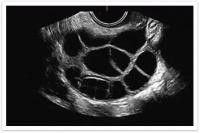

医生检查过后表明曼丽想要自然怀孕机会渺茫,

对于一些无法自然生育的夫妻,试管婴儿技术就是福音了。但做试管婴儿也是有一定条件的: